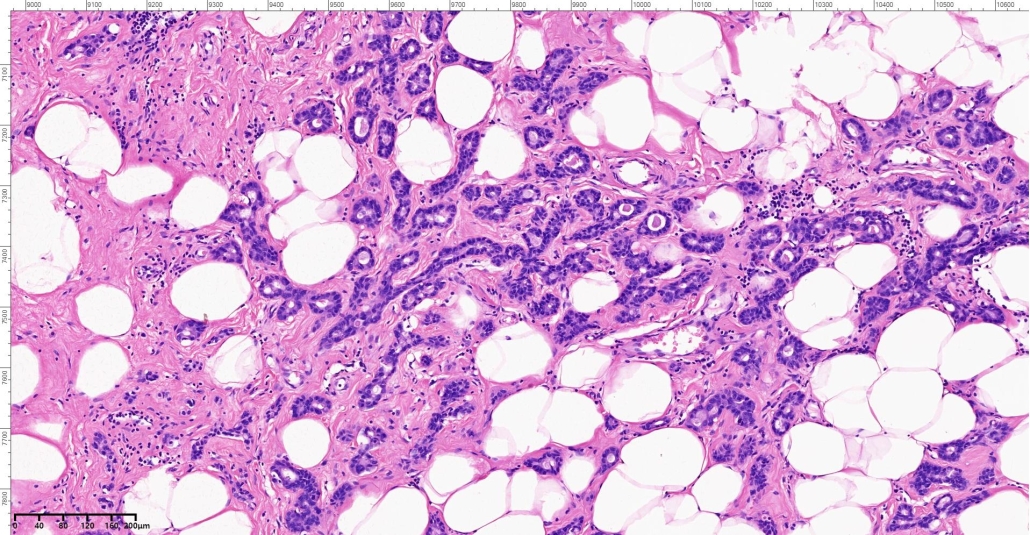

A 46-year-old woman presents with a slowly enlarging, non-tender palpable lump in the upper outer quadrant of the breast. Mammography shows an ill-defined density without calcifications. Local excision is performed.